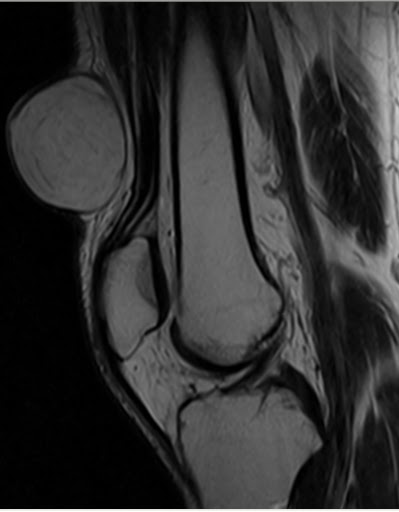

При осмотре атерома представляет собой опухолевидное образование округлой формы, мягкой консистенции размером от 5 до 40 мм и более. Кожа над атеромой обычно не изменена, однако в случае присоединения воспаления может иметь красноватый оттенок. Атерома подвижна вместе с окружающими тканями, безболезненна. Атерома может оставаться маленькой на протяжении многих лет, либо увеличиваться.

Иногда атерома сообщается с поверхностью кожи через небольшое отверстие, через которое могут отделяться атероматозные массы. Часто атеромы нагнаиваются, кроме этого, может происходить разрыв атеромы в подкожную клетчатку.